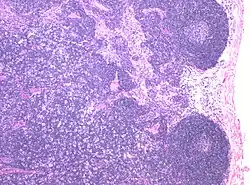

![]() | Follicular lymphoma | Micrograph showing a small B-cell lymphoma compatible with follicular lymphoma. H&E stain. | Category: Histopathology of follicular lymphoma | Follicular lymphoma |